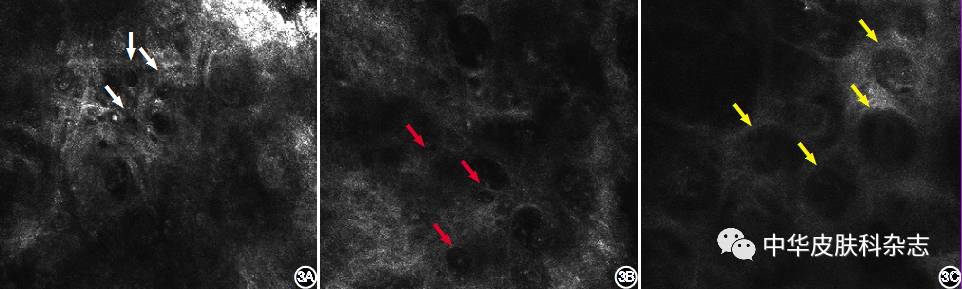

图3 Paget病患者反射式共聚焦显微镜图像 3A:表皮结构紊乱,表皮浅层甚至角质层出现暗色空泡样结构(深度10 μm,水平0.5 mm × 0.5 mm)(白色箭头); 3B:棘层内可见大量空泡样细胞,其大小为正常棘细胞的2倍以上,中央是中等亮度的细胞核,周围细胞质为低亮度(红色箭头)(深度50 μm,水平0.5 mm × 0.5 mm); 3C:基底层可见巢状结构(黄色箭头)(深度90 μm,水平0.5 mm × 0.5 mm)

结果显示,5例Paget病患者,RCM图像可见表皮结构紊乱,正常的蜂窝状结构消失,棘层内可见单个或成巢分布的Paget样细胞。不典型的Paget细胞表现为空泡样结构,典型的Paget细胞表现为靶环样细胞或细胞簇,对应组织学图像的单个Paget细胞或小细胞巢,大小为正常棘细胞的2倍以上,中央是中等亮度的细胞核,周围呈低亮度暗色圈;

另外,Paget病组织学上大量的Paget细胞在基底层融合成细胞巢,在RCM图像中往往呈现为低折光的巢状结构,该结构大小相对一致,折光相对均匀;不同于湿疹基底层正常的蜂窝状结构及明亮的色素环。